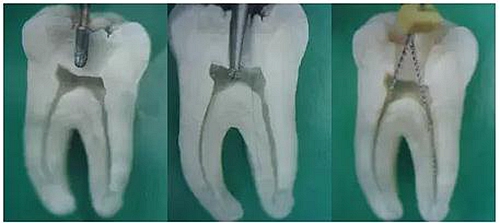

1.開(kāi)髓:洞型是否制備的符合要求,髓室頂是否揭得剛剛好,沒(méi)有破壞洞壁及洞底結(jié)構(gòu)。

圖1裂鉆鉆到近髓 圖2球鉆穿髓 圖3小號(hào)銼探查根管口

圖4 球鉆揭髓頂 圖5修整洞型 圖6完成開(kāi)髓